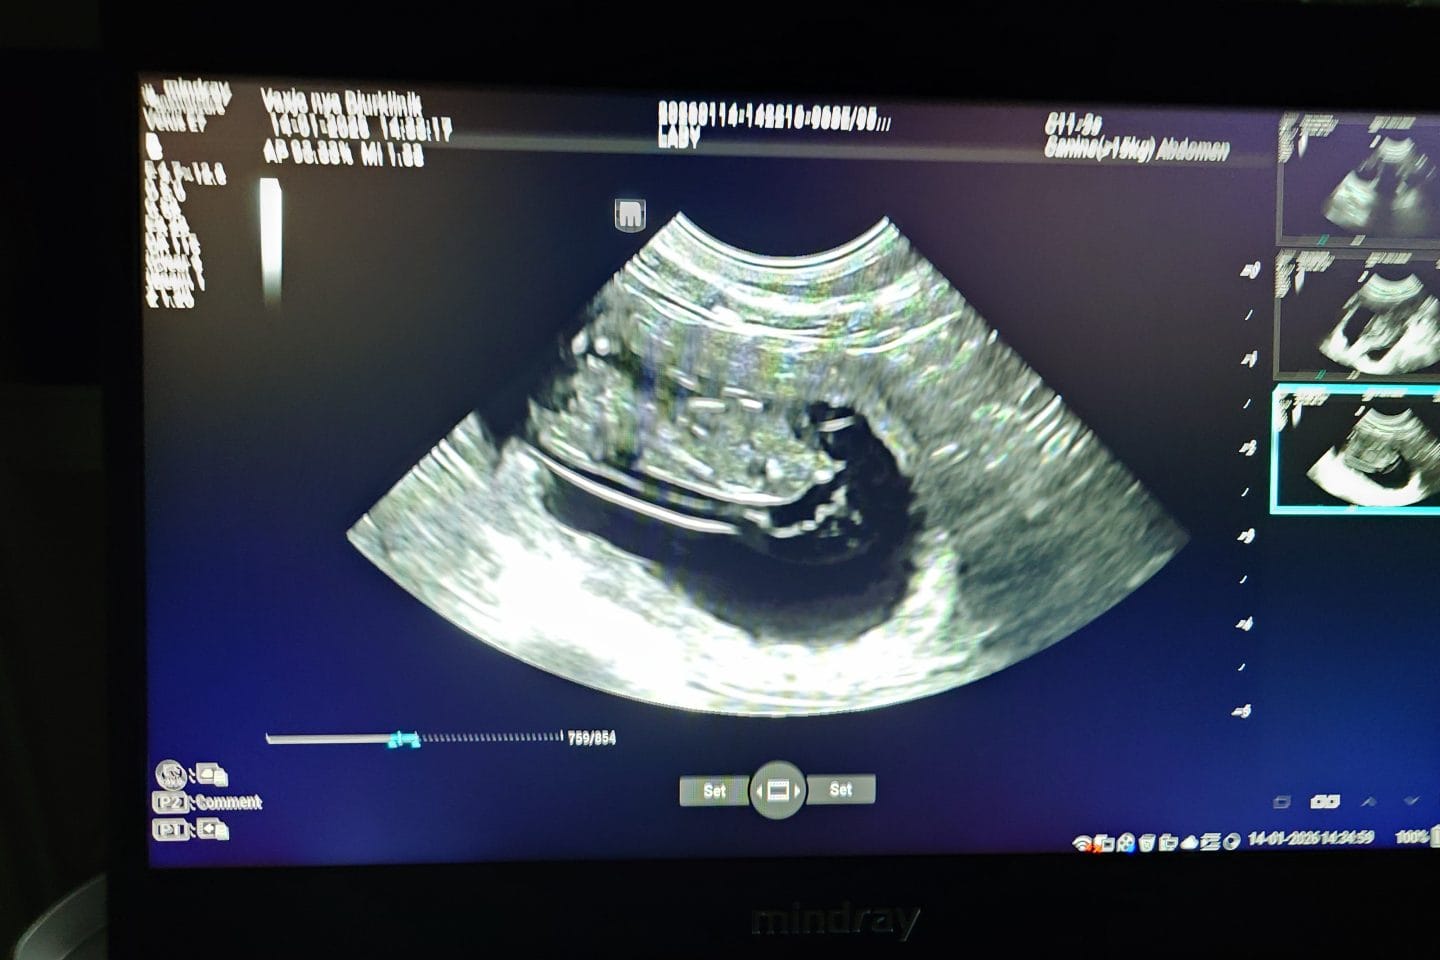

Lady är konstaterat dräktig

Lady Glenriska Morgana är nu ultraljudsundersökt och konstaterat dräktig med Crack of Dawn New Quest, Nemo. Det är med stor glädje och förväntan vi ser fram emot denna valpkull som beräknas göra...